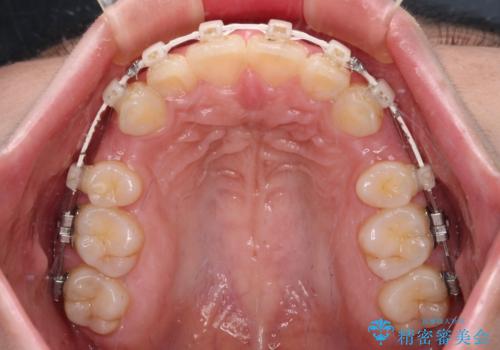

- 飛び出した上顎前歯と、閉じにくい唇、口元の突出した印象の横顔を気にして来院された患者様です。

骨格的な上顎前突であり、上下前歯の前後的な距離が大きいため、上顎は左右第一小臼歯を、下顎は左右第二小臼歯をそれぞれ2本抜歯することで前歯が接触するようにし、さらには奥歯の咬み合わせも、より理想的な状態へ近づけていくこととしました。

3年以上はかかる難症例であるため、表側のワイヤー装置にて治療を行うこととしました。